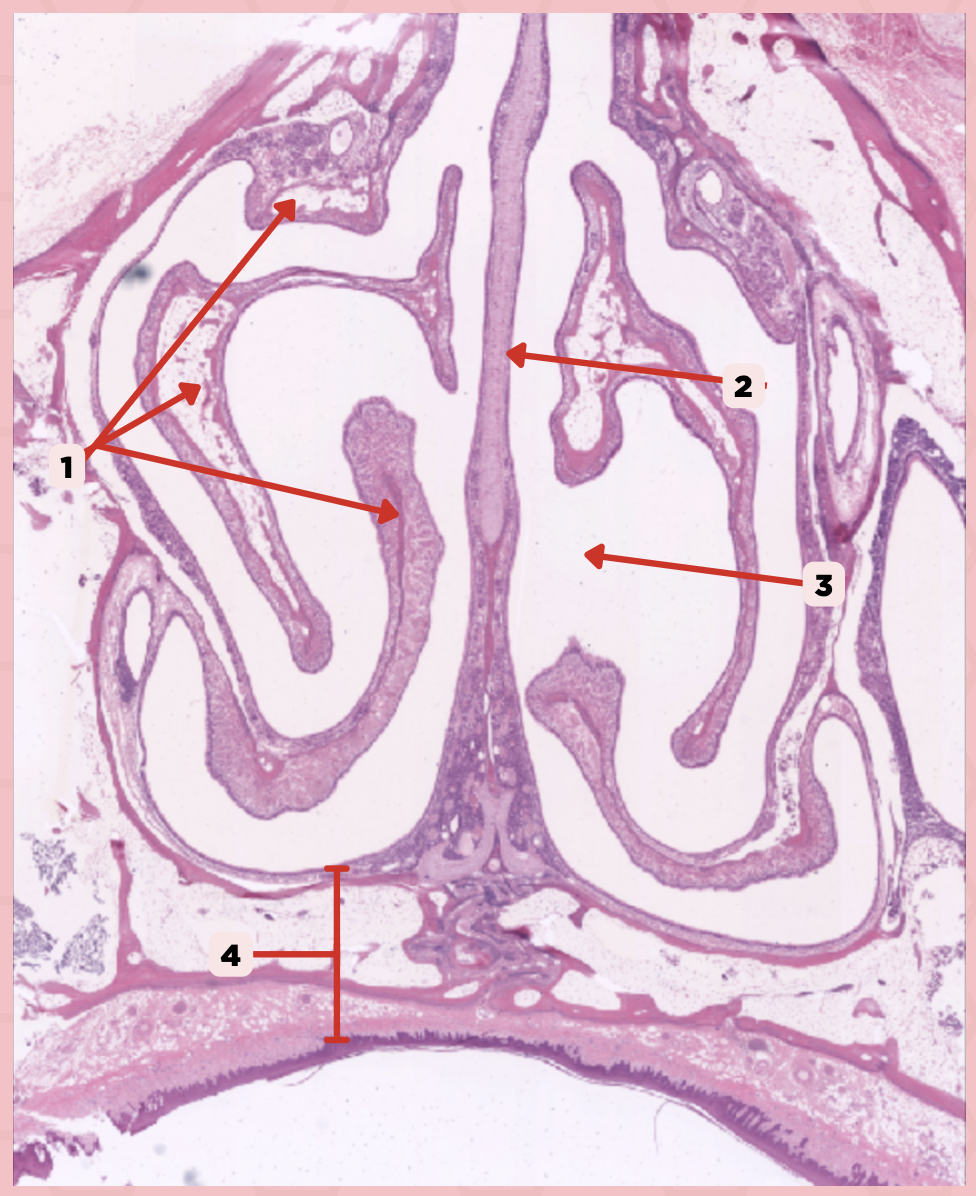

Nasal Cavity

What are the spaces found immediately lateral to #2?

Nasal Turbinates (conchae)

Identify the structure labeled as 1.

Nasal septum

Identify the structure labeled as 2.

Nasal cavity

Identify the structure labeled as 3.

Hard palate

Identify the structure labeled as 4.

Mucosal Associated Lymphoid Tissue (MALT)

What time of lymphocyte is numerous in the nasal cavity?